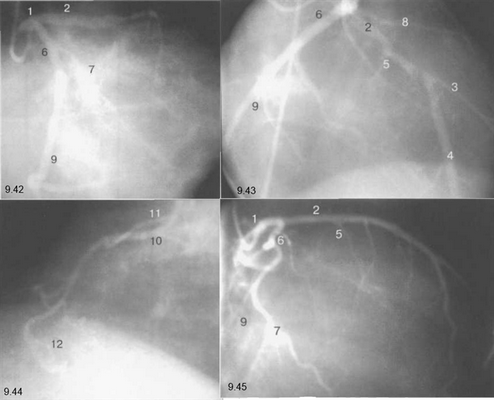

На рис. 9.37—9.41 изображены левая и правая коронарные артерии и их ветви при равномерном типе коронарного кровообращения в обычной последовательности проекций.

На следующих рисунках представлены два типа коронарного кровообращения — правый и левый и характеризующиеся неравномерным развитием правой коронарной и огибающей (ветвь левой коронарной артерии) артерий. При левом типе отмечается выраженная периферия огибающей артерии при значительной гипоплазии правой коронарной артерии. При правом типе чаще всего хорошо развита маргинальная ветвь и гипоплазирована основная ветвь огибающей артерии. Периферия правой коронарной и, в особенности, правая левожелудочковая ветвь значительно выражены и превосходят огибающую по размерам зоны кровоснабжения.

Рис. 9.42-9.44 — левый тип коронарного кровообращения.

Рис. 9.45 и 9.46 — правый тип коронарного кровообращения.

Рис. 9.42. Левая коронарная артерия. Правая косая проекция.

Рис. 9.43. Левая коронарная артерия. Проекция «паук».

Рис. 9.44. Правая коронарная артерия. Левая косая проекция.

Рис. 9.45. Левая коронарная артерия в правой косой проекции.

Рис. 9.46. Правая коронарная артерия в переднезадней проекции.

Здесь и на рис. 9.38—9.46:

1 — левая коронарная артерия; 2 — проксимальная треть передней нисходящей артерии; 3 — первая диагональная ветвь передней нисходящей артерии; 4 — дистальная часть передней нисходящей артерии; 5 — септальная ветвь передней нисходящей артерии; 6 — проксимальная часть огибающей артерии; 7 — первая маргинальная ветвь огибающей артерии; 8 — промежуточная артерия; 9 — дистальная часть огибающей артерии; 10 — проксимальная часть правой коронарной артерии; 11 — ветвь синусного узла правой коронарной артерии; 12 — ветвь острого края правой коронарной артерии; 13 — бифуркация правой коронарной артерии; 14 — правая левожелудочковая ветвь правой коронарной артерии; 15 — задняя нисходящая ветвь правой коронарной артерии.